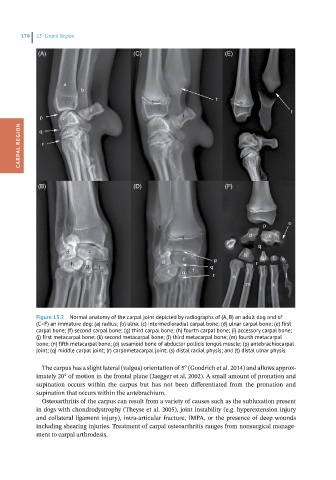

Figure 13.2 Normal anatomy of the carpal joint depicted by radiographs of (A, B) an adult dog and of

(C–F) an immature dog: (a) radius; (b) ulna; (c) intermedioradial carpal bone; (d) ulnar carpal bone; (e) first

carpal bone; (f) second carpal bone; (g) third carpal bone; (h) fourth carpal bone; (i) accessory carpal bone;

(j) first metacarpal bone; (k) second metacarpal bone; (l) third metacarpal bone; (m) fourth metacarpal

bone; (n) fifth metacarpal bone; (o) sesamoid bone of abductor pollicis longus muscle; (p) antebrachiocarpal

joint; (q) middle carpal joint; (r) carpometacarpal joint; (s) distal radial physis; and (t) distal ulnar physis.